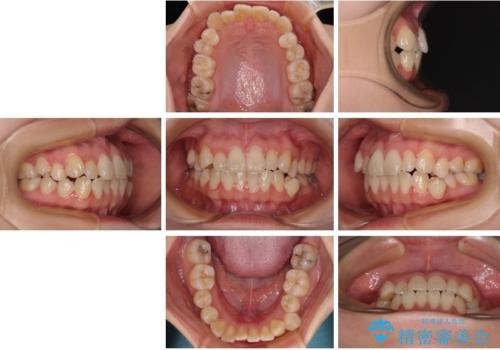

- 20代女性

- 1年6ヶ月

- 10-30回

- 患者様は「歯並び全体のデコボコが気になり、人前で笑うことに抵抗がある」とのことでご来院されました。

診査の結果、上下顎ともに叢生が認められましたが、ワイヤー矯正・マウスピース矯正のいずれでも対応可能な症例でした。

という患者様のご希望を踏まえ、プラスチックブラケット+コーティングワイヤーを用いたワイヤー矯正を選択しました。

金属色が目立ちにくく審美性が高い

確実に歯を動かせるため治療計画が立てやすい

といったメリットがあります。